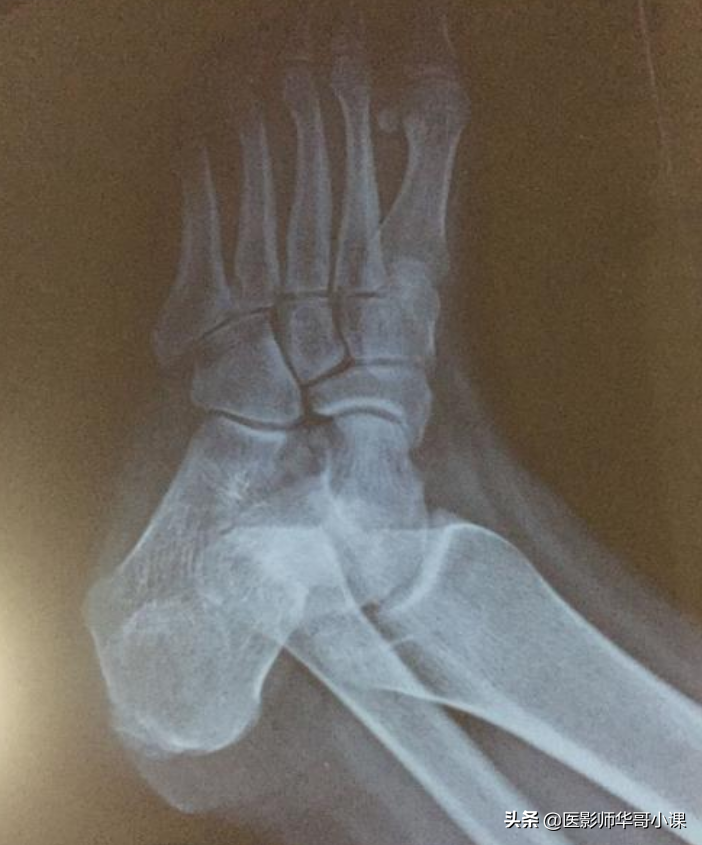

第四节足与踝

1趾骨骨骺骨化中心往往为多个小骨化核,外缘不规则。第二,三,五趾末节趾骨骨骺的二次骨化中心可永不出现。

2.末节趾骨的远端稍肥大,边缘不整齐,为正常现象。

3.基节趾骨跖面肌腱附着处,在侧位片上表现为边缘不整齐。

4.趾骨和跖骨,这些小管状骨的继发骨化中心常由若干小骨块组成,在它们出现后若干年内都呈边缘粗糙的不规则阴影,第一趾跖关节处常有一个或两个籽骨,一个籽骨有时可分为两半,不可误为骨折。在发育期间,第五跖骨近端骺软骨外侧可能出现一个阶梯状二次骨化中心,多数为双侧,数年后与跖骨愈合,也可终生不愈合。

5.跖骨近端互相重叠,甚似骨折线,两个跖骨近端可能融合为一,而无跖骨功能不全的症状。

6.跖骨近端可有多余的化骨核,和掌骨一样。

7.舟状骨化骨核发生在生后六个月开始钙化,早期多不整齐或不规则,这种现象可能持续数月或数年之久,仅在一侧发生,在足舟骨结节处的副骨最为多见,一般为双侧性,少数单侧。

8.在舟距关节近端,距骨背缘上的皮雷氏骨,不要误认为碎骨。

9.距骨后结节下缘可能有一副骨即三角骨,这个副骨可能和距骨愈合,也可能是永远分离的。

10.骰骨的化骨核在早期是多个不规则小化骨核,楔状骨的化骨核在早期也可以是不规则的。

11.婴儿和儿童的跟骨后缘是不整齐的,跟骨结节的化骨核最初多为不整形的分节状,以后又较其它部分致密,均为发育中的正常现象。跟骨体偶可有两个独立的或多个骨化中心,二者之间的软骨带在融合前颇似骨折线。

12.跟骨滑车突顶端的二次骨化中心,在外旋和内翻45度角摄片时很似碎骨片。

13.七岁以上儿童的足部侧位上,在跟骨滑车的骨质中能见到一个圆形或三角形的假性囊肿样透亮阴影,此因骨松质稀疏所致。

14.载距小骨足副骨中极其罕见的一种,发生于跟骨载距突的上方。

15.胫骨远端可能出现一个单独分离的内踝化骨核,腓骨外踝部也可有一个单独的化骨核。

16.胫骨骨干远端外侧面面有一条沟槽即腓骨切迹。